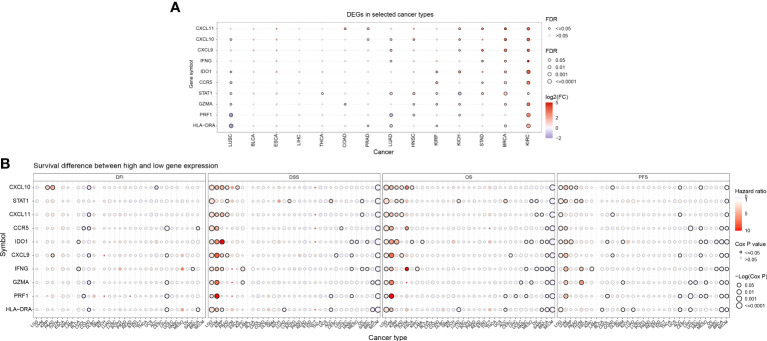

The Supplementary Figure 1 shows the flow chart of this study. Initially, we conducted an analysis of gene expression profiles associated with IFN-γ in various cancers and observed variations in their expression levels across different tumor types. Using a heat map, we examined the expression of 10 IFN-γ-associated genes in 33 distinct cancer types and discovered discrepancies in gene expression within the same tumor as well as across different tumor types. Notably, TGCT, LUSC, LUAD, KIRC, HNSC, DLBC, and CHOL exhibited high expression of the studied genes, while UVM, PCPG, LGG, KICH, and ACC showed low expression (f1). In terms of prognostic implications, we found that high expression of most of the selected 10 genes was associated with shortened progression-free survival (PFS), overall survival (OS), and disease-free survival (DSS) in patients with LGG and UVM, indicating increased risk. Conversely, SKCM patients with high gene expression had higher DSS, OS, and PFS, suggesting a protective effect (all P < 0.05). Additionally, high STAT1 expression was linked to higher DSS and OS in patients with PAAD or ACC (f1). These findings indicate that the expression of IFN-γ-associated genes is correlated with the prognosis of tumor patients, with the correlation depending on the specific tumor type.

Prognostic significance of IFN-γ score in tumor